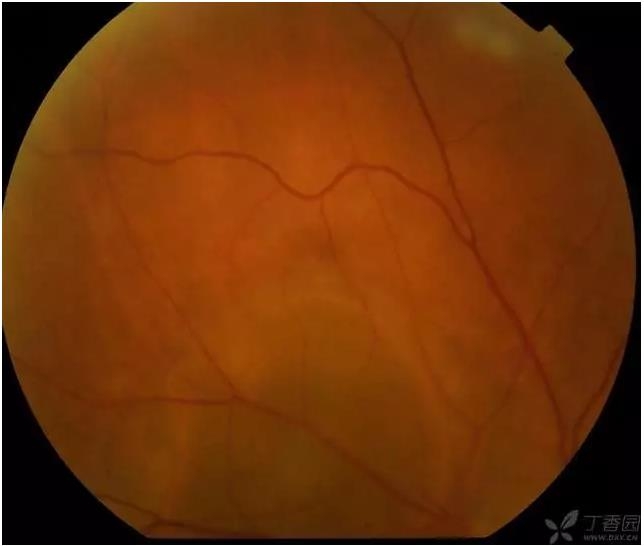

▼孔源性视网膜脱离